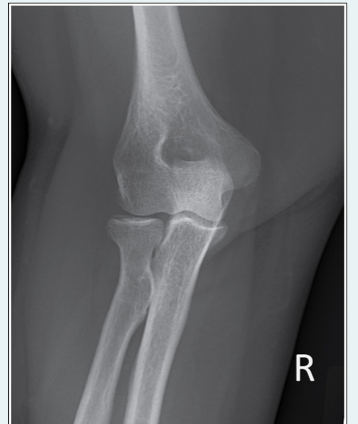

Which, from the following list of image criteria, is not met with this AP elbow image?

a.CR is not perpendicular with the IR

b.Hand is supinated

c.Equal demonstration of humerus and forearm

d.Arm is not extended

A